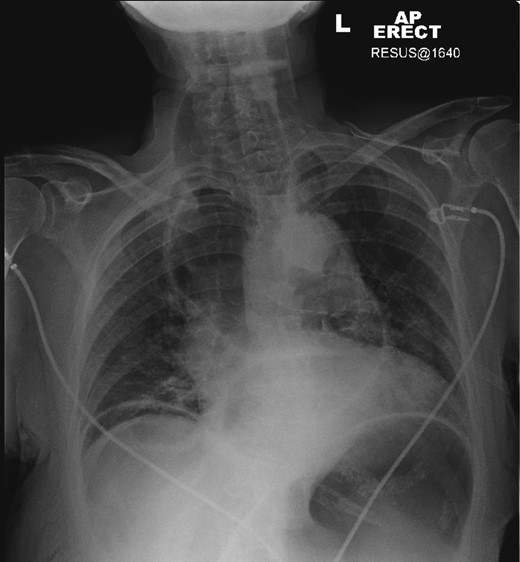

A plain chest radiograph was taken demonstrating a massively dilated air and fluid-filled oesophagus, with no visible intraparenchymal lung abnormality. A 16-French gauge nasogastric tube was immediately placed into the oesophagus with aspiration of air, fluid and food debris. This resulted in almost immediate relief of the patient's respiratory distress, and she clinically improved.